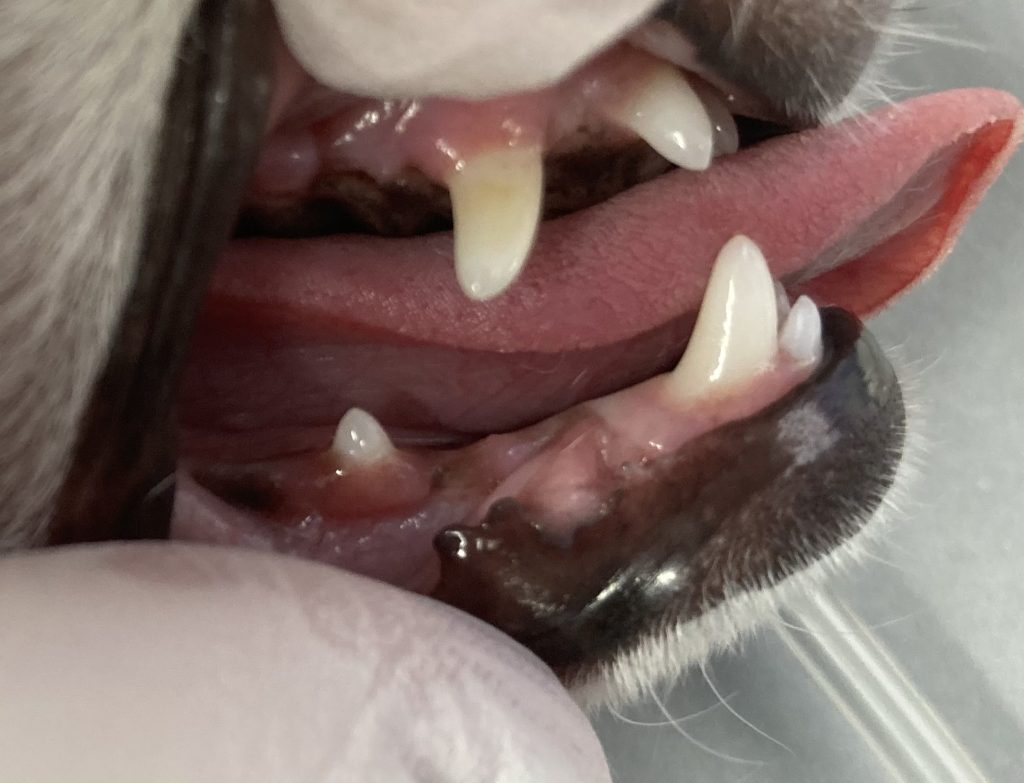

この症例は上記のリスクを精査するために、鎮静麻酔下での精密検査を行いました。